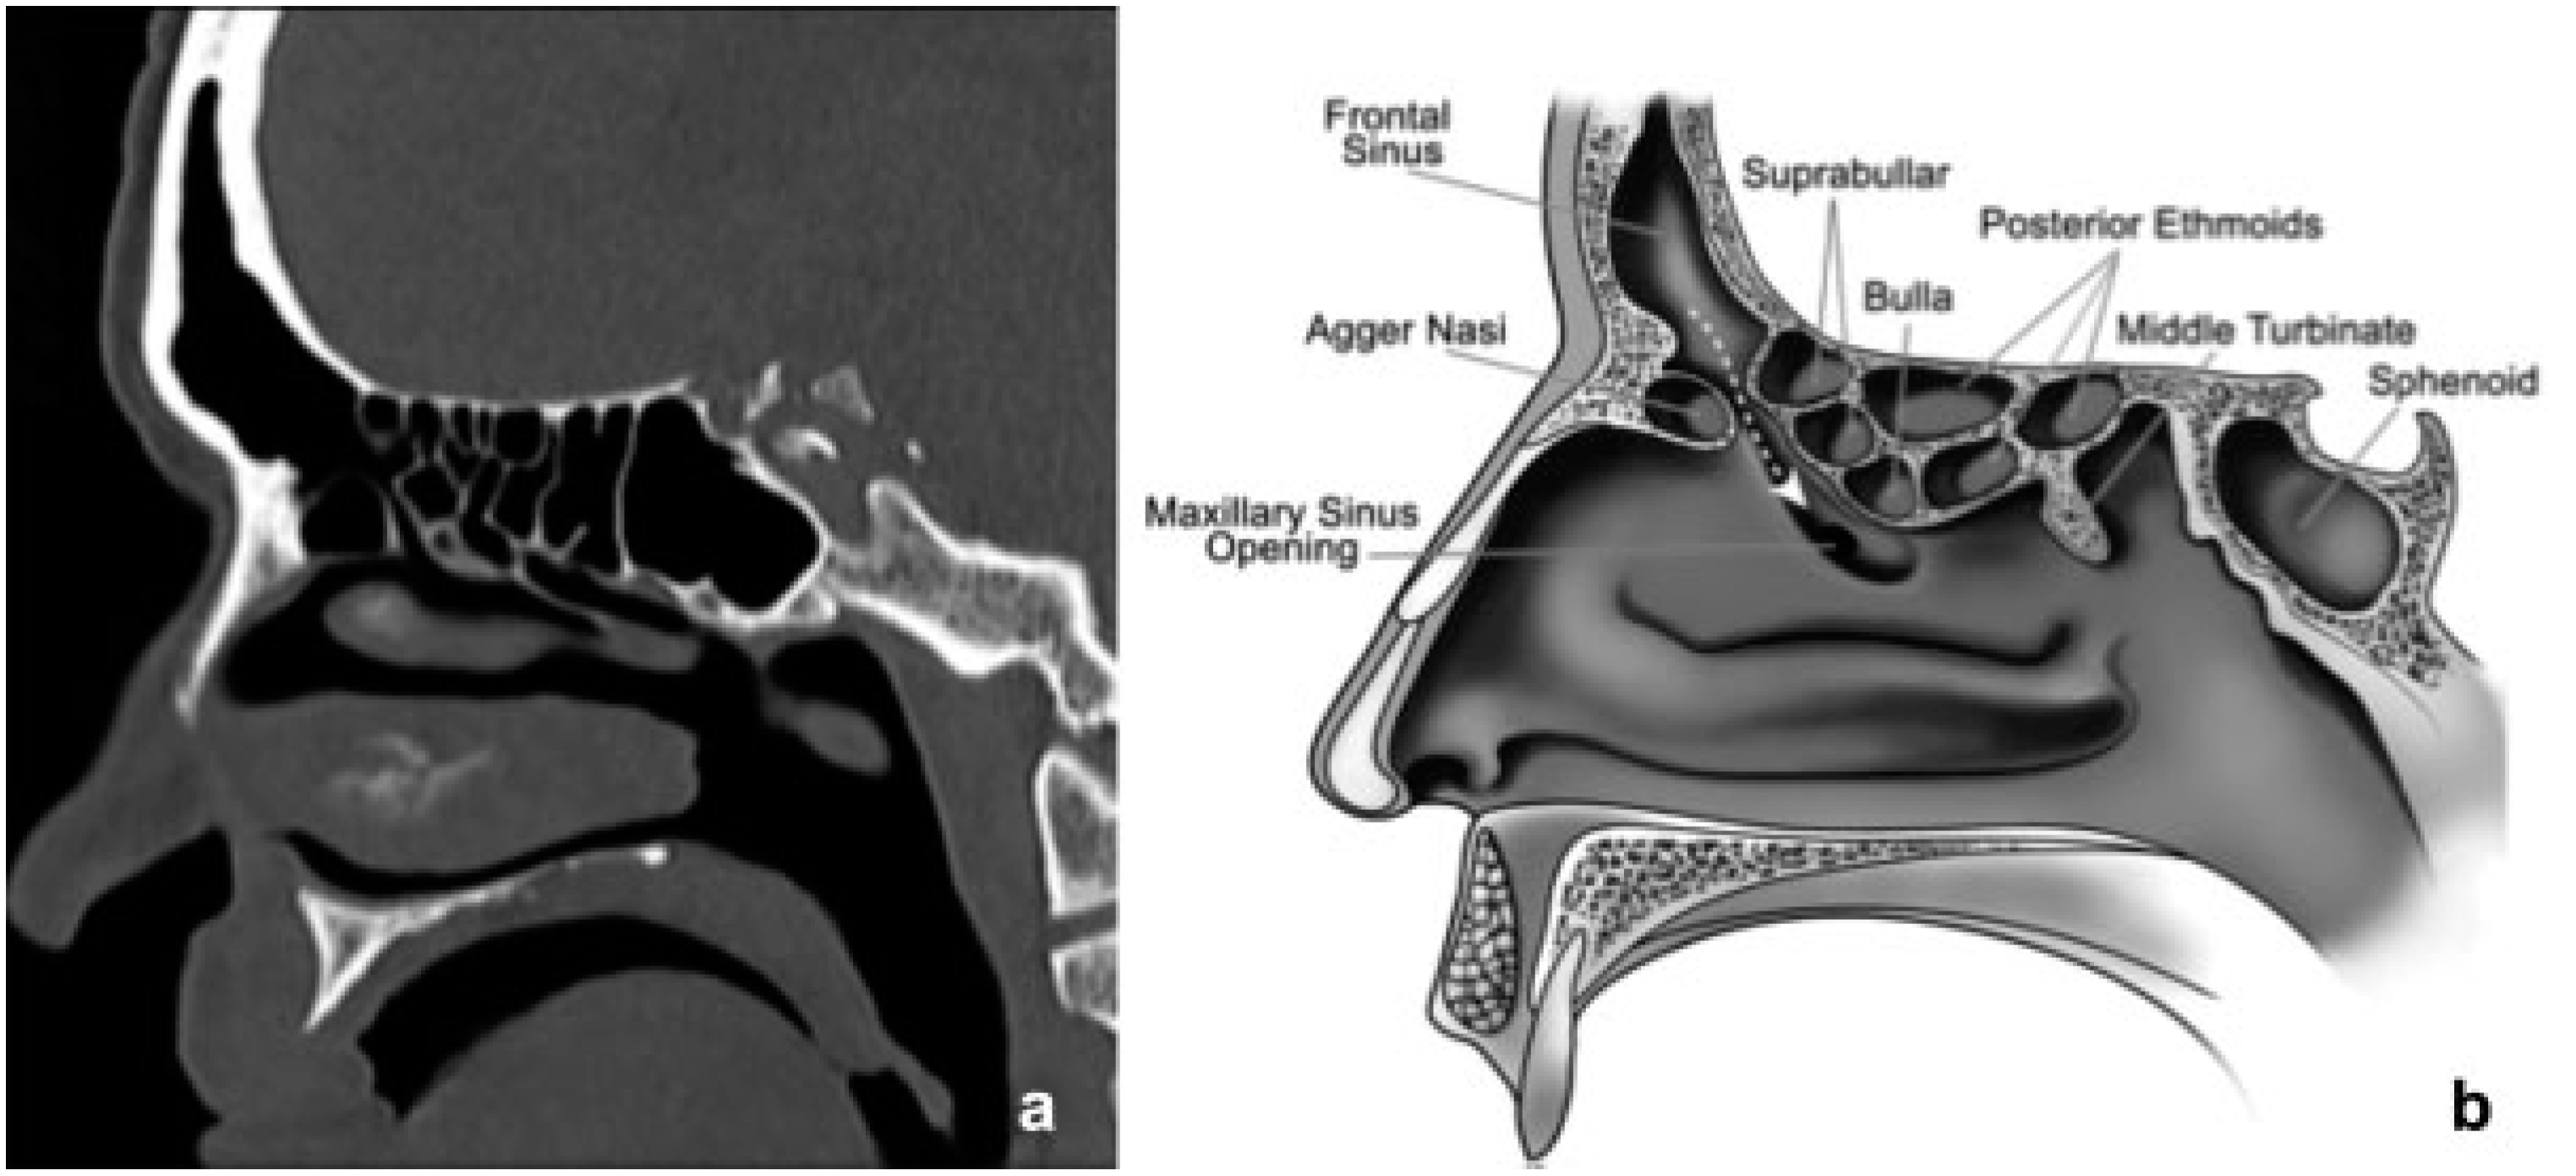

The frontal sinus outflow tract (FSOT) is an hourglass shape, made up of the infundibulum superiorly, the frontal recess inferiorly, and separated by the ostium or narrowest portion (3–4 mm). There are a variety of pneumatization patterns of ethmoidal cells that are adjacent to the FSOT.[13] The FSOT is found in the posterior, inferior, and medial portion of the frontal sinus. (Figure 1).

Figure 1.

(a) CT in the sagittal plane of the frontal sinus outflow tract (FSOT). (b) Corresponding illustration of the frontal sinus outflow tract (dotted arrow) bordered anteriorly by the agger nasi cell and posteriorly by the suprabullar and bullar cells.